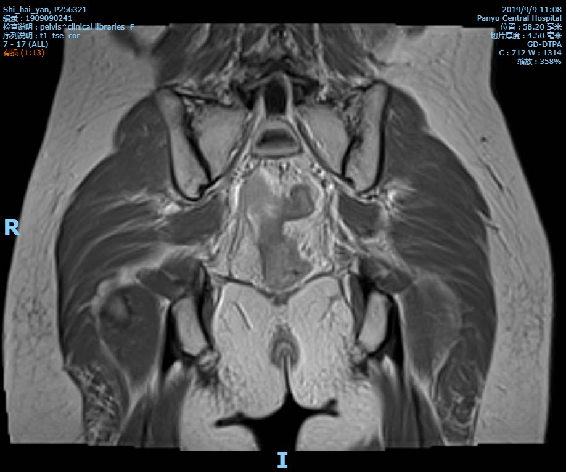

2019-09-09复查盆腔MR示直肠全段管壁不均匀增厚,以中段较明显,最厚处约12mm,较前改善,仍考虑累及浆膜面,不除外直肠前筋膜受累。

放化疗后影像学: